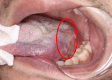

Case presentation: A 33-year-old Chinese man presented with a progressively enlarging mass at the base of his left tongue. Contrast-enhanced computed tomography and magnetic resonance imaging revealed an augmented soft tissue mass in the left jaw region with indistinct boundaries, enlargement of cervical lymph node of uncertain etiology, and no evidence of distant metastasis. A transoral needle biopsy from the mass pathologically revealed low-grade mucoepidermoid carcinoma. Complete transoral excision and cervical lymph node dissection were performed, followed by reconstruction with an anterolateral thigh free flap. Examination of the obtained surgical specimen confirmed low-grade mucoepidermoid carcinoma with MAML2 gene fusion in the base of the tongue. The tumor was removed with negative margins, and the cervical lymph nodes were free of disease. The patient had an uneventful recovery and showed no evidence of recurrence or metastasis at 40 months of follow-up.